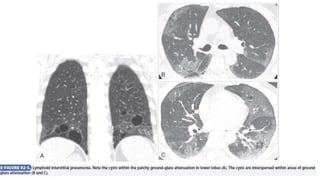

Cryptogenic Organizing Pneumonia

Cryptogenic organizing pneumonia, previously referred to as

Diagnosis

• Cryptogenic organizing pneumonia most commonly manifests as a

• Chest radiography reveals patchy unilateral or bilateral alveolar

opacities that may be peripheral or migratory; small nodular opacities

• In about 90% of patients, HRCT shows areas of air space consolidation

with lower lung zone predominance, frequently in a subpleural or

peribronchial distribution other features include small nodules along

bronchovascular bundles and ground-glass attenuation. BAL is

nonspecific; increased lymphocytes, neutrophils, and eosinophils may

be seen. On biopsy, key histologic features are excessive proliferation

of granulation tissue within the small airways and alveolar ducts as

well as chronic inflammation in the surrounding alveoli.